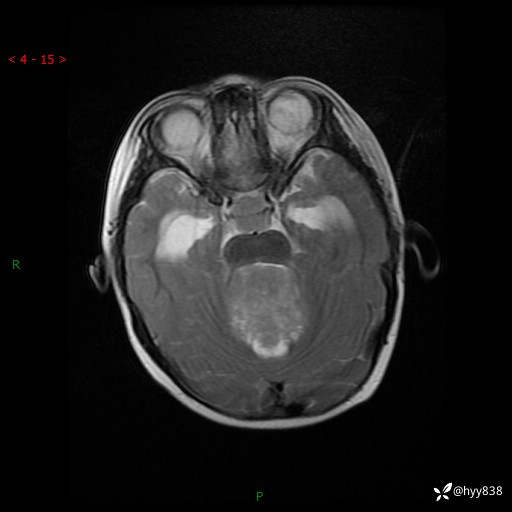

理解“经典”,从经典病例开始,3岁小女孩,行走不稳2个月,加重1个月--结果公布

性别:女

年龄:3岁

简要病史:发现行走不稳2个月,加重1个月

颅脑MRI平扫+增强

三脑室、四脑室多发病变,如何分析?